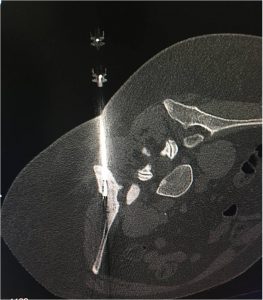

No tratamento do osteoma osteóide, é realizado através da inserção de uma agulha, através da pele (sem cortes), no interior da lesão óssea, guiado por tomografia computadorizada ou fluoroscopia. O procedimento tem curta duração e é considerado por muitos o método de primeira escolha. Usualmente o paciente recebe alta hospitalar após 3-24horas.

Posicionamento das agulhas guiado por tomografia.